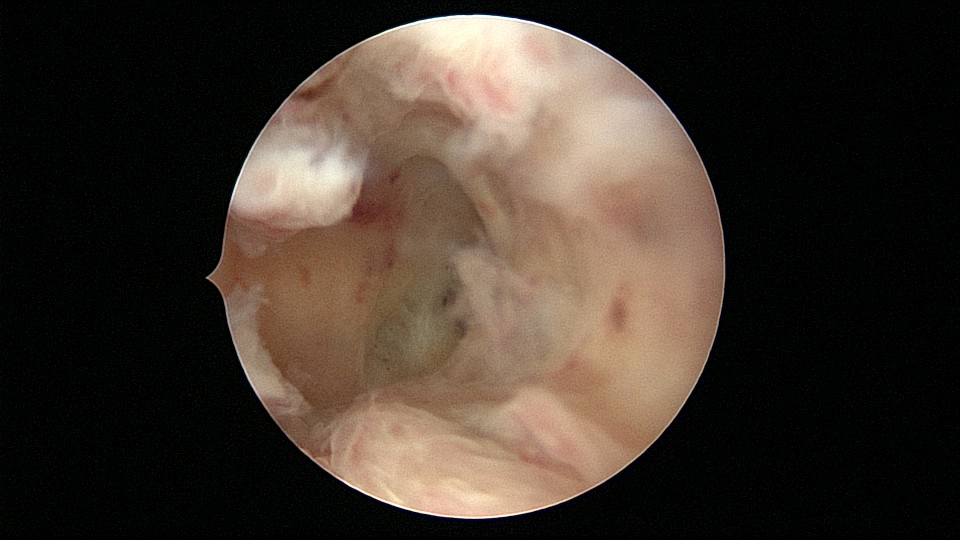

患者33岁,G5P2,顺产2次,胎停清宫后月经量减少,外院B超提示宫腔粘连。2021年5月宫腔镜探查,宫腔重度粘连,宫腔狭小,右侧输卵管开口可见,左侧输卵管开口未见,单极电针分粘,恢复宫腔形态,显露左侧输卵管开口(僵硬)。2021年6月宫腔镜二探取球囊,宫腔形态正常,双侧输卵管开口可见,宫内膜薄。2022年7月自然妊娠,2023年3月孕39+周顺产分娩。现38岁,G6P3,顺产3次。